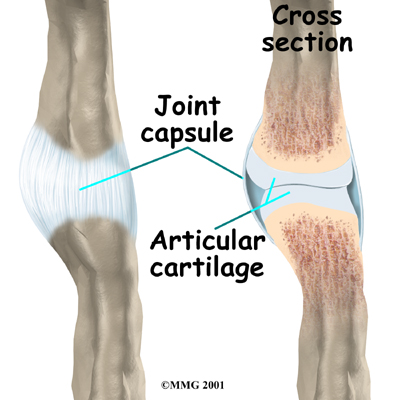

Ligaments are tough bands of tissue that connect bones together. Several ligaments hold the joints together in the finger. These ligaments join to form the joint capsule of the finger joint. The joint capsule is a watertight sac around the joint. The joint surfaces are covered with a material called articular cartilage. This material is the slick, spongy material that allows one side of a joint to slide against the other joint surface easily. When this material wears out, the joint develops a type of arthritis called osteoarthritis and becomes painful. Rheumatic arthritis is a different form of arthritis (which develops due to an autoimmune disorder and is more widespread in the body) but can also cause wearing out of the joint surfaces and also deformity of the joints.